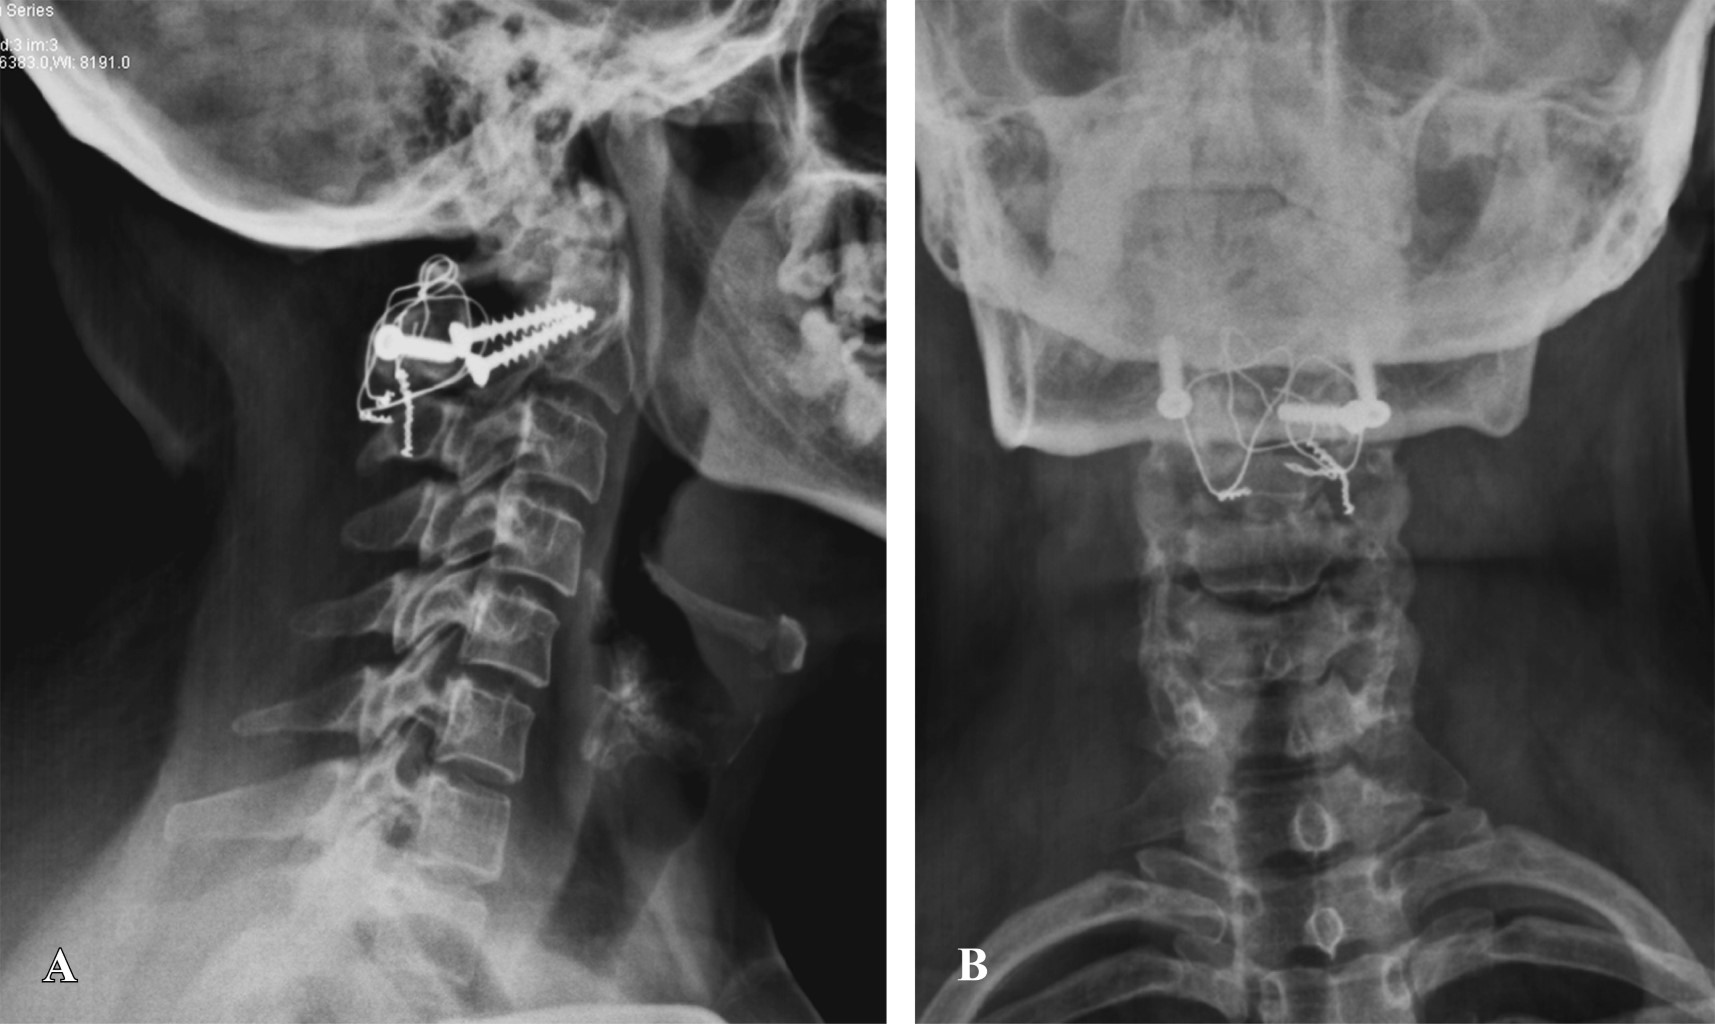

The os odontoideum is a variable oval or round ossicle with a smooth cortical border, which partially corresponds to the odontoid process, without having continuity with the rest of C2 bone. The multifactorial etiology causes instability and clinically translates into pain and compression data into neural structures. The treatment of choice is surgical and techniques have been developed that focus on preserving the stability of the segment. We present the case of a 23-year-old female patient, who begins to suffer at 8 years of age, refers to moderate to severe cervicalgia, which develops with paresthesias in the left hemisphere and later paresis of the left thoracic limb. Physical examination showed hypoaesthesia of the left hemisphere, as well as paresis of the left thoracic limb. Extension studies demonstrate chronic axonal lesion from C1 to C3, predominantly left, imaging studies showing axial instability and magnetic resonance bulbar compression. The patient receives surgical treatment consisting of posterior fixation C1-C2, evolving satisfactorily.

Figure 1